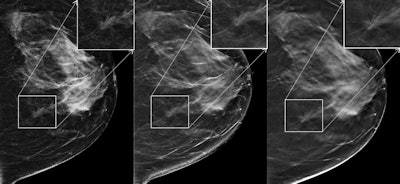

One solution is creating 2D mammography images from the 3D DBT data -- so-called "synthesized" 2D images -- via commercially available software. To evaluate the technique, a team led by Dr. Per Skaane, PhD, from the University of Oslo compared the diagnostic performance and radiation dose of conventional FFDM plus DBT with that of synthesized 2D images plus DBT for breast cancer screening.

Synthesized 2D exams produced during the first period were generated by an early version of C-View, while those in the second period were generated by an upgraded version, the authors wrote.

Having 2D mammography images in addition to the tomosynthesis images is important for many reasons, including the ability to compare priors to current exams, compare the right versus left breast, and provide current 2D exams to other institutions, according to Skaane and colleagues. And the evolution of synthesized 2D image software has made the use of these images with DBT even more viable for clinical practice.